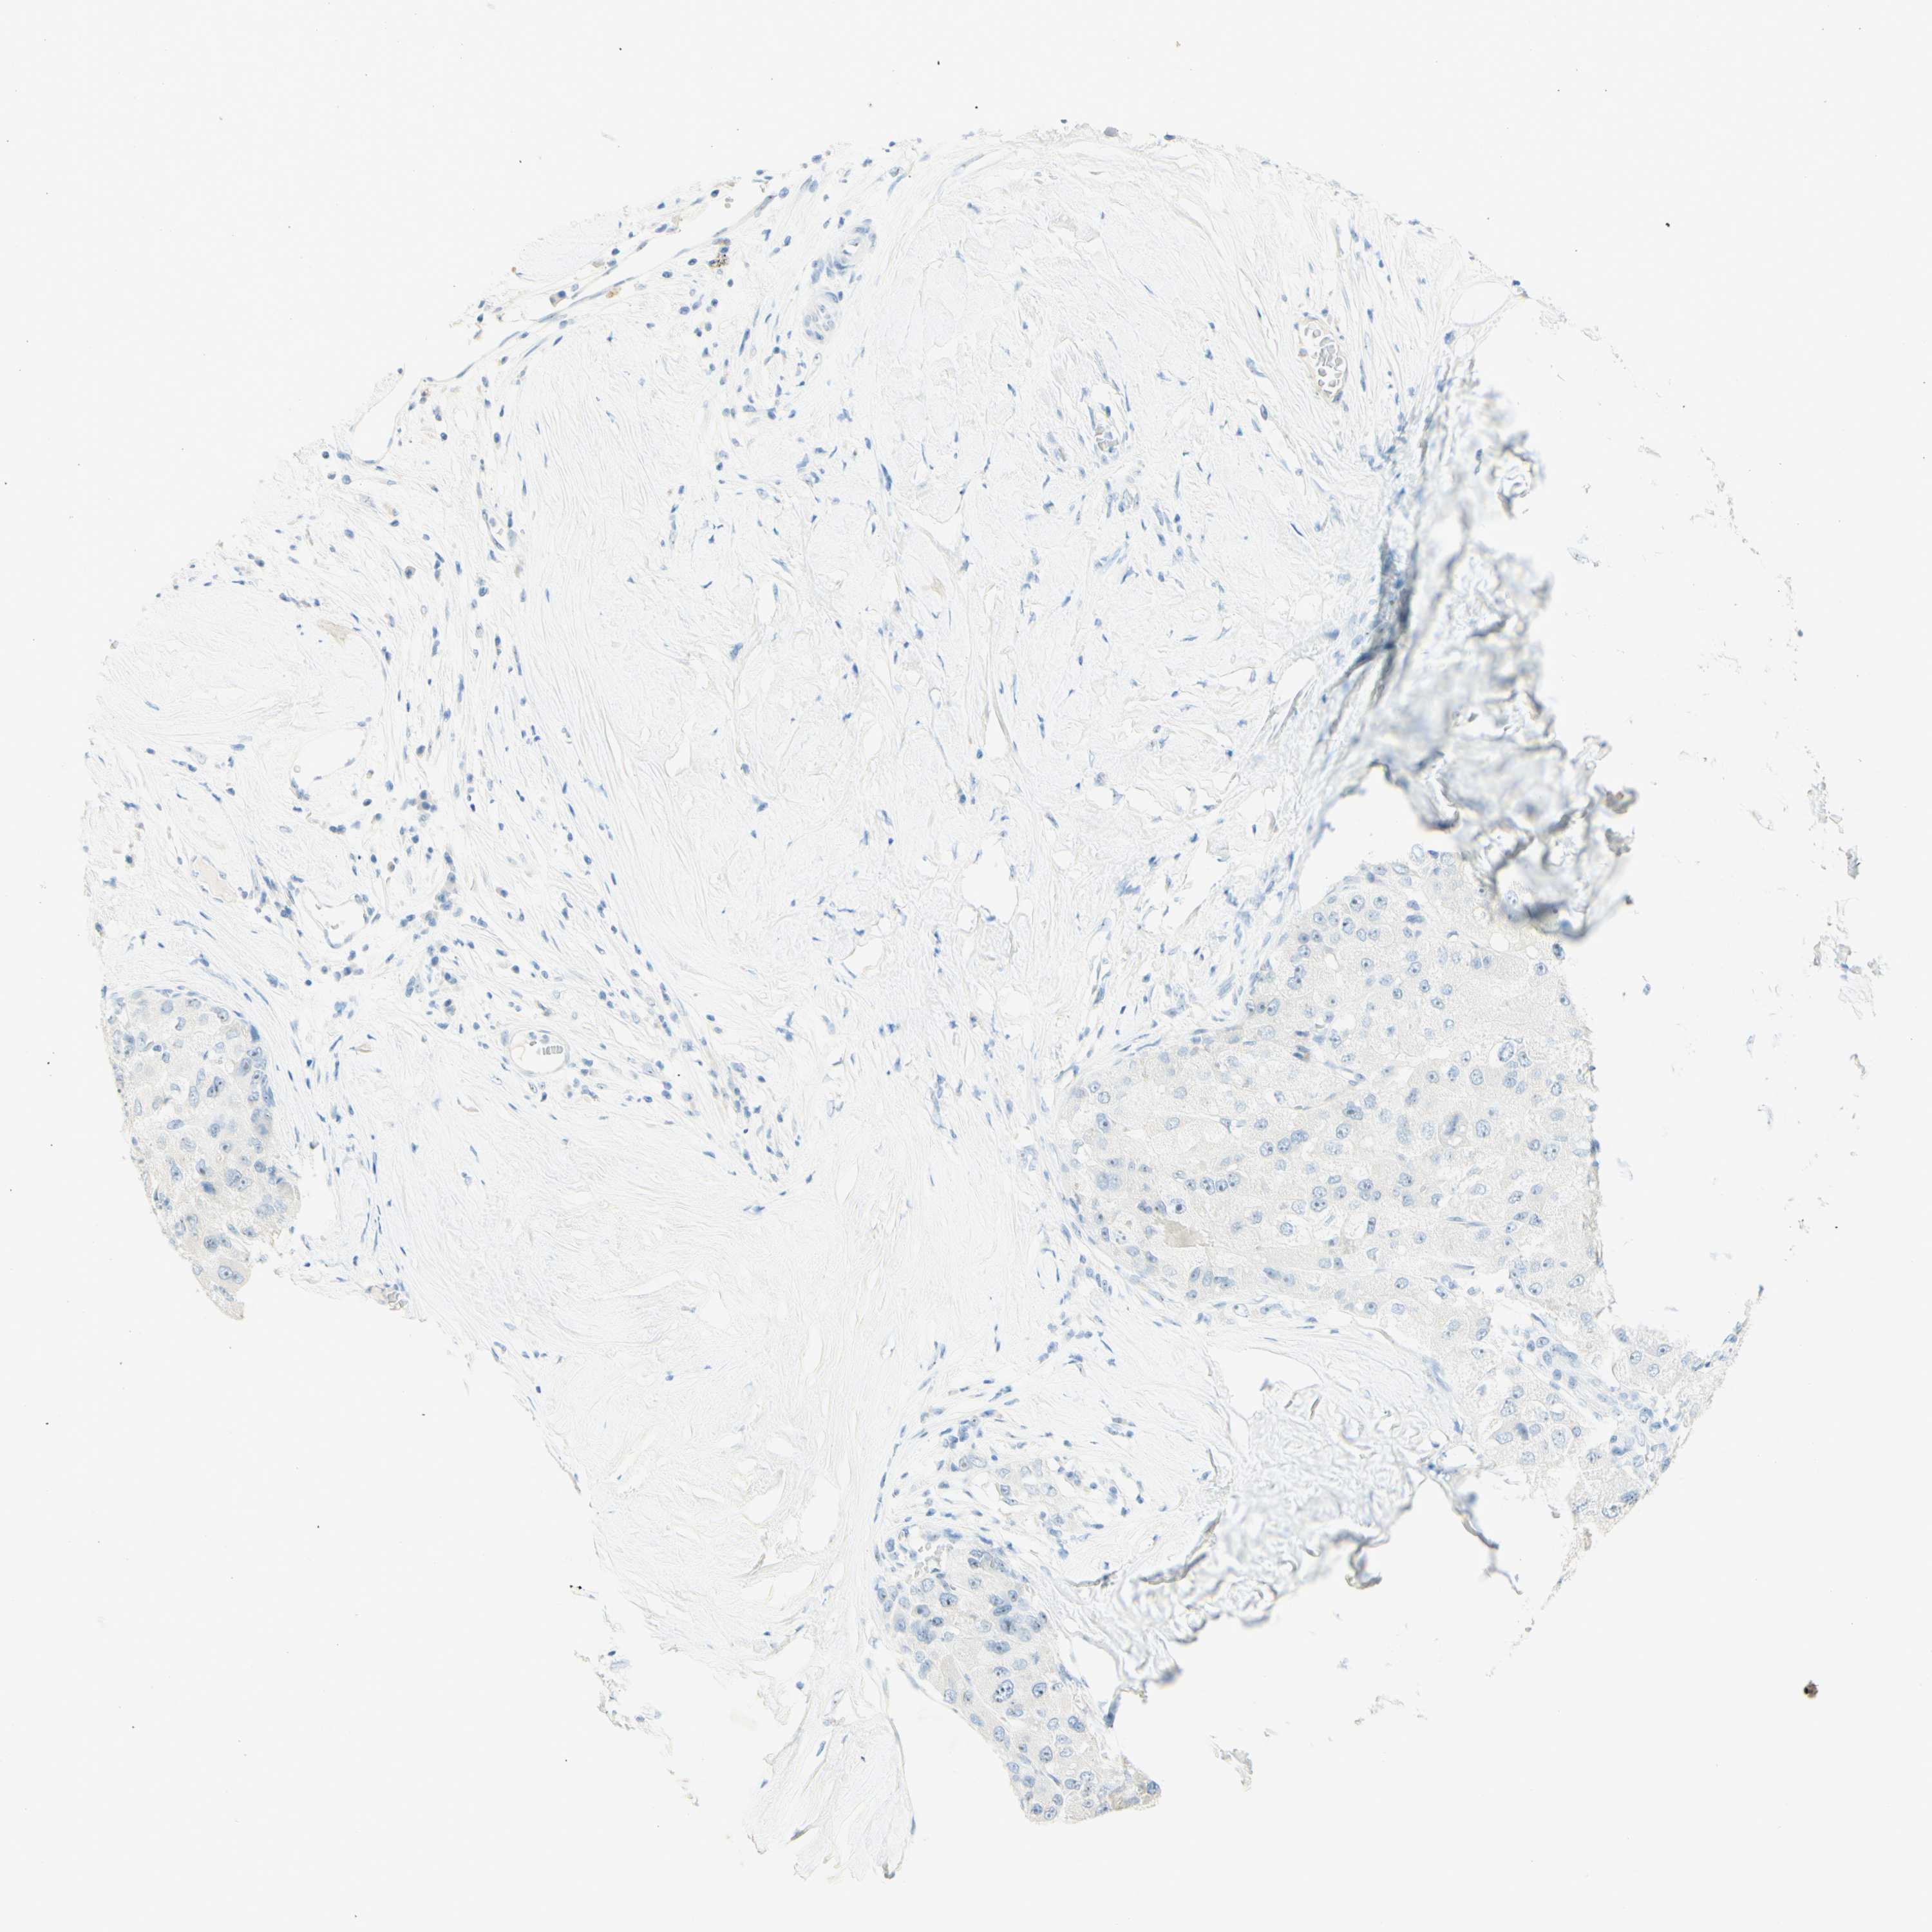

LIVER CANCER - Protein expressioni

A mouse-over function shows sample information and annotation data. Click on an image to view it in a full screen mode. Samples can be filtered based on level of antibody staining by selecting one or several of the following categories: high, medium, low and not detected. The assay and annotation is described here.

Note that samples used for immunohistochemistry by the Human Protein Atlas do not correspond to samples in the TCGA dataset.

Antibody stainingi

Antibody staining in the annotated cell types in the current human tissue is reported as not detected, low, medium, or high, based on conventional immunohistochemistry profiling in selected tissues. This score is based on the combination of the staining intensity and fraction of stained cells.

Each image is clickable and will lead to virtual microscopy that enables deeper exploration of all samples and also displays staining intensity scores, fraction scores and subcellular localization as well as patient and tissue information for each sample.

Antibody HPA011284

Antibody CAB026403

Cholangiocarcinoma

Carcinoma, Hepatocellular, NOS